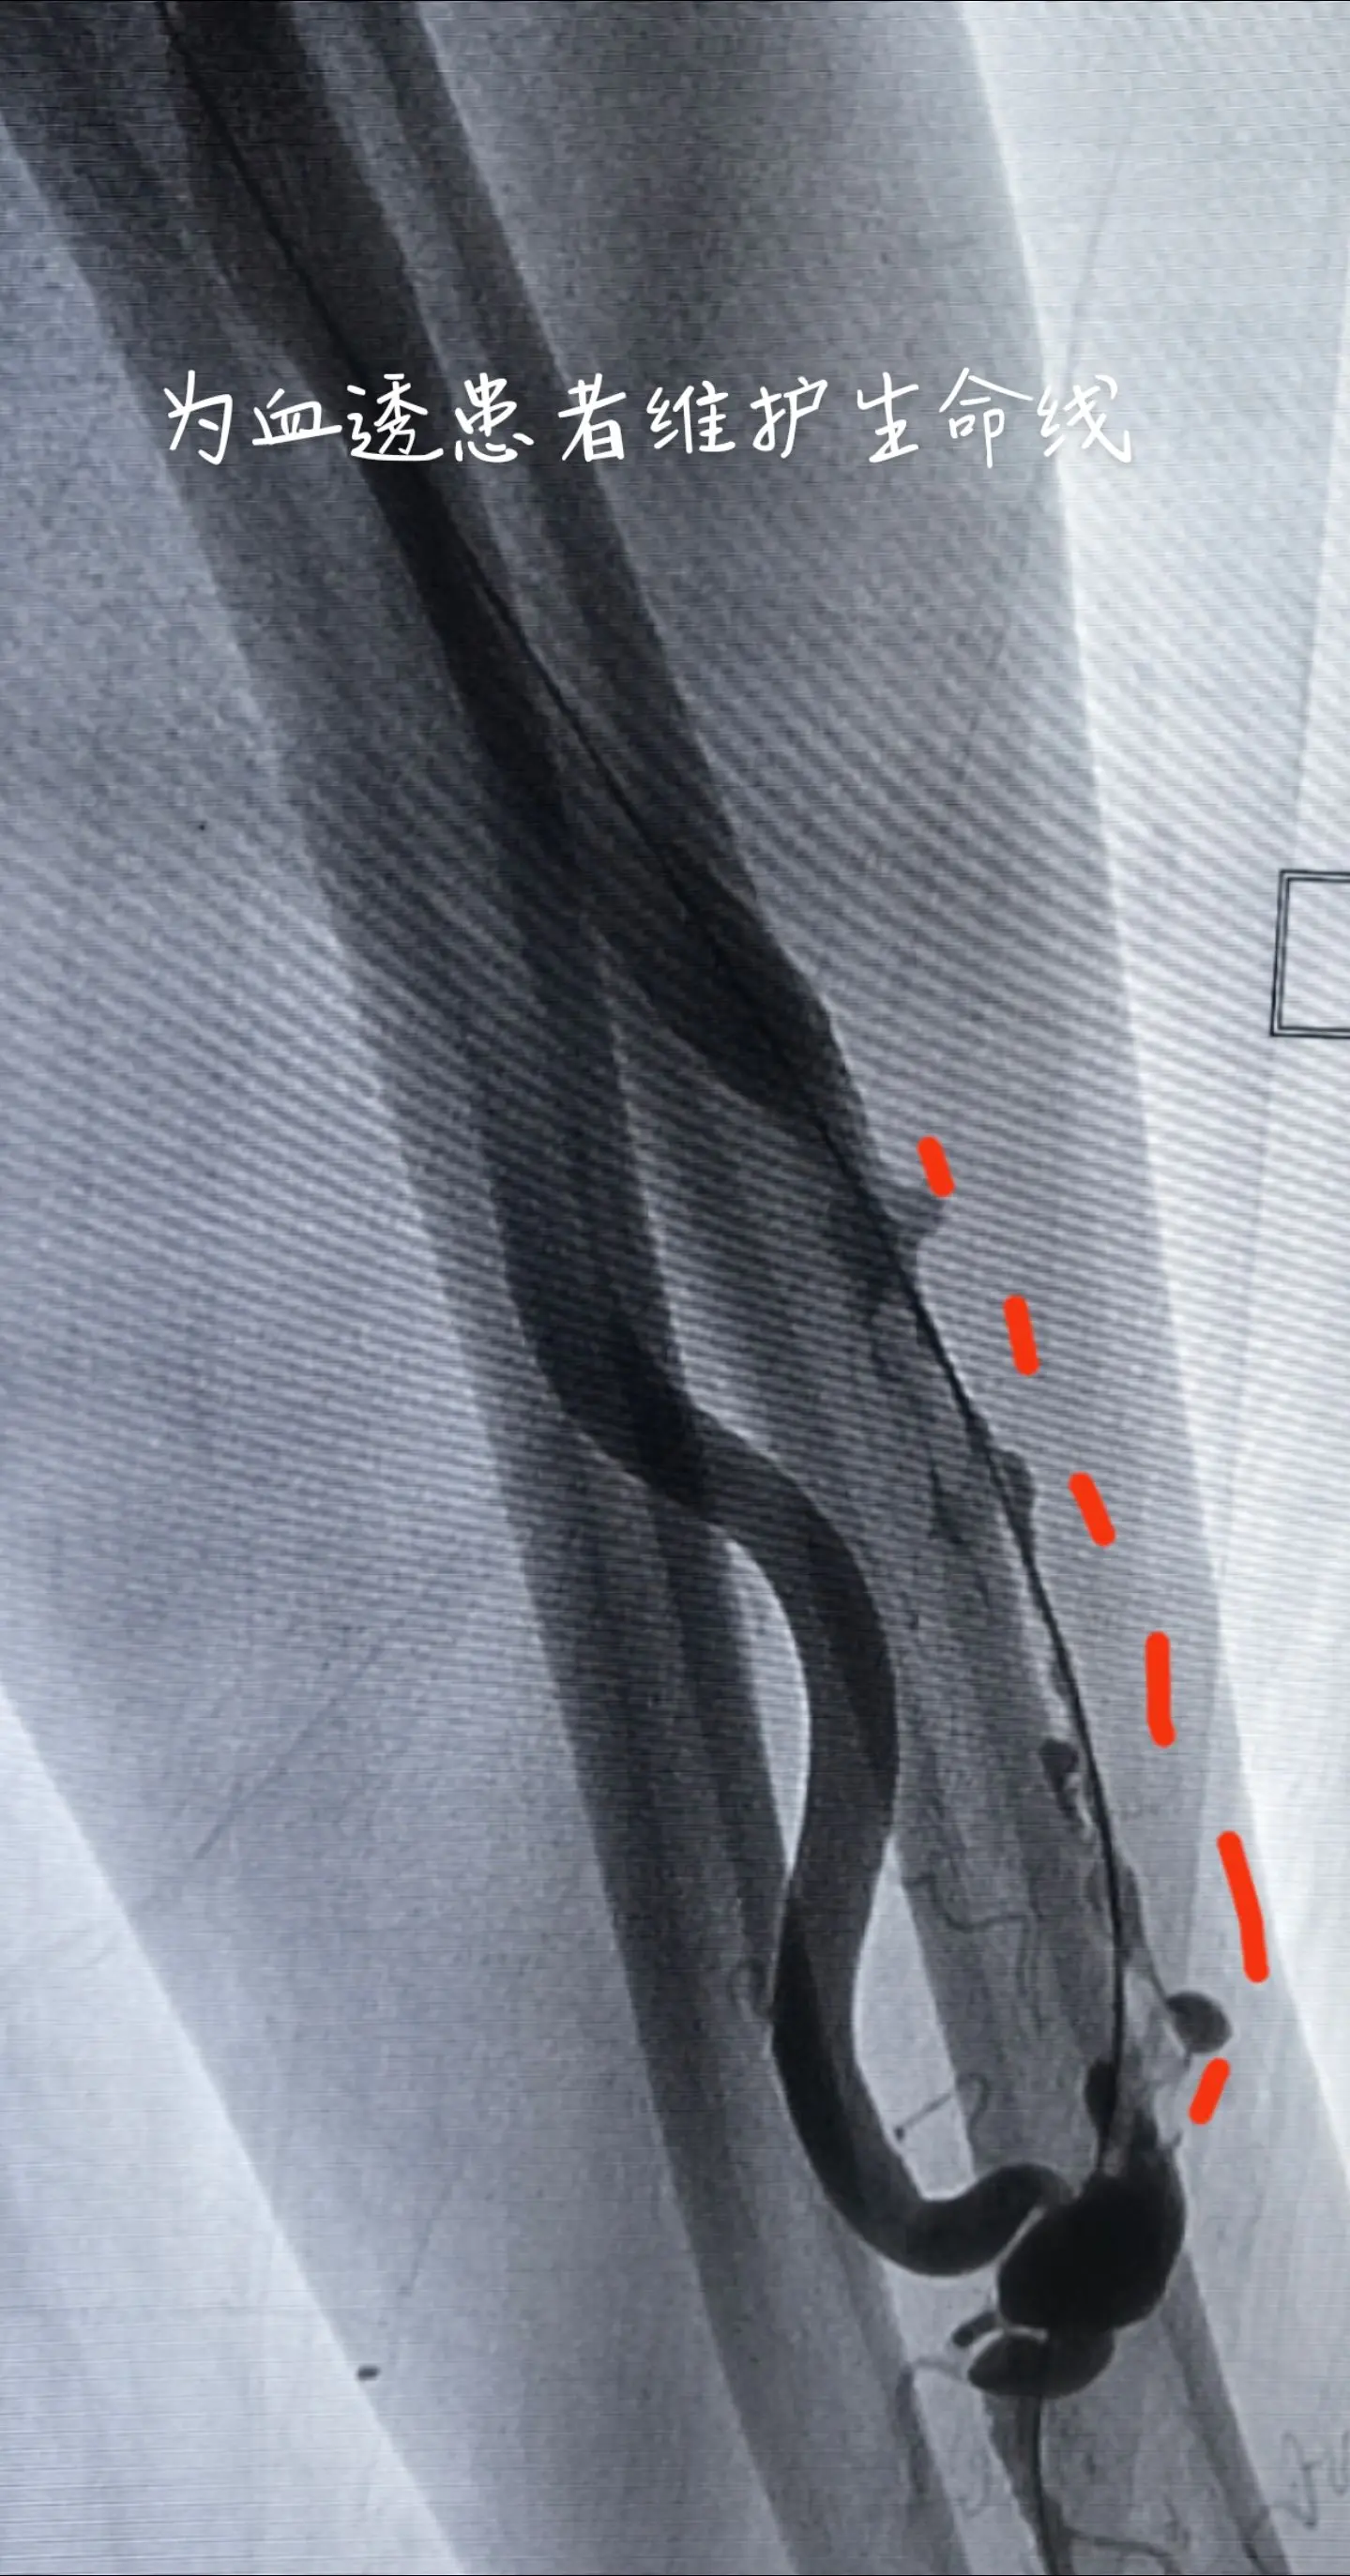

为血透患者维护生命线